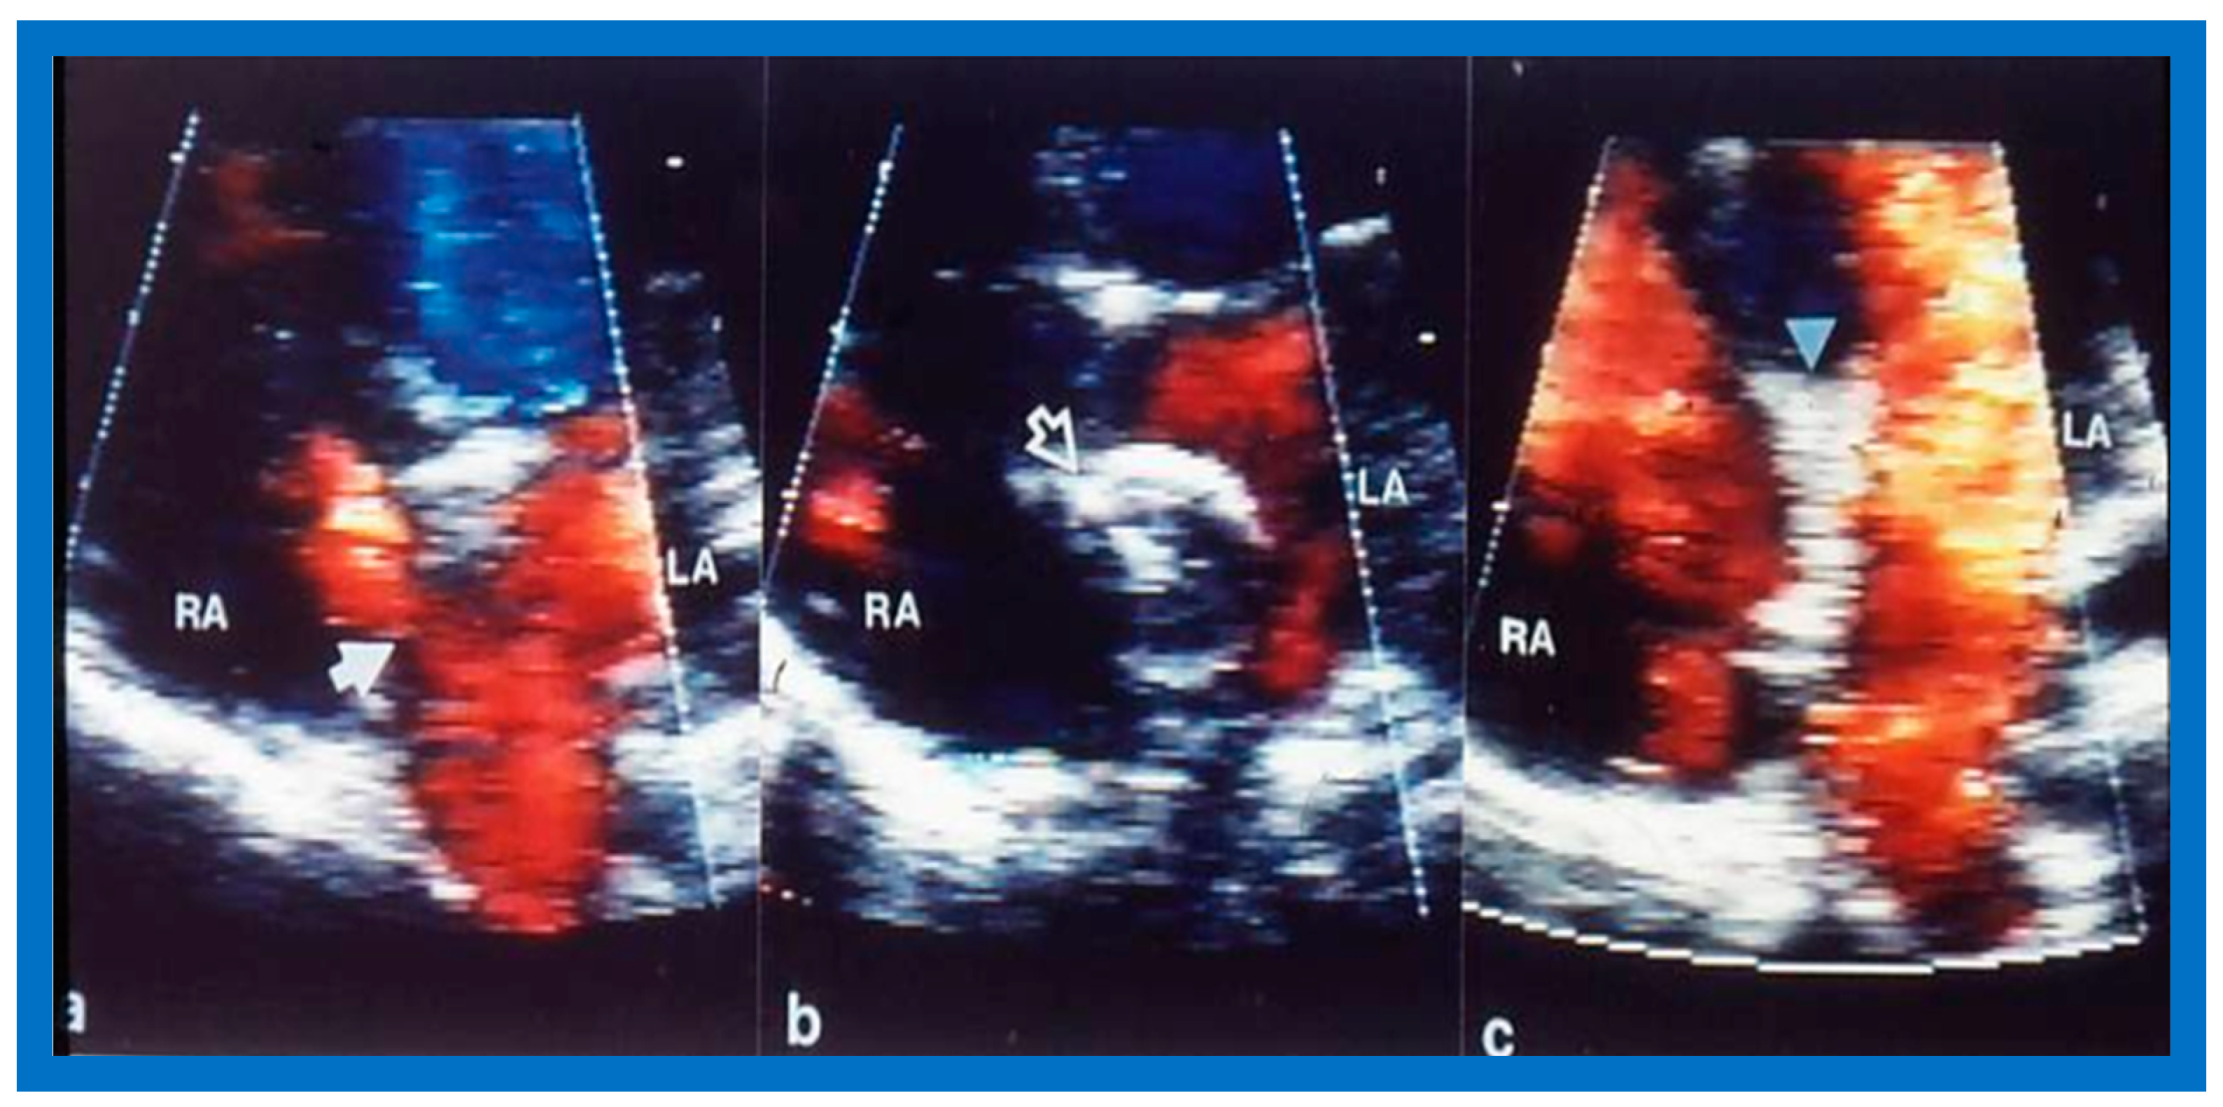

9. Follow-Up after Device Occlusion

9.4. Residual Shunts